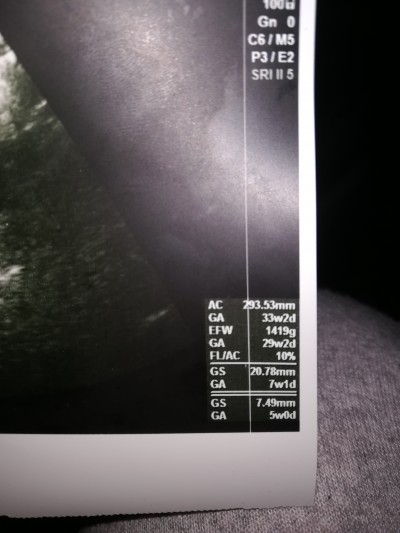

Kızlar 6 Haftalıgım son adet tarihine göre kese degeri nasıl? Ben anlamadım doktor daha minicik dedi gülümsedi sadece aklım gitmiş ki soramadım o an

Siz bunun 6 haftalık görüntü olduğuna emin misiniz?

5 haftalık bu zaten sağ Altta da yazıyor

EFW yani kilosu da 1419 gram yazıyor :))